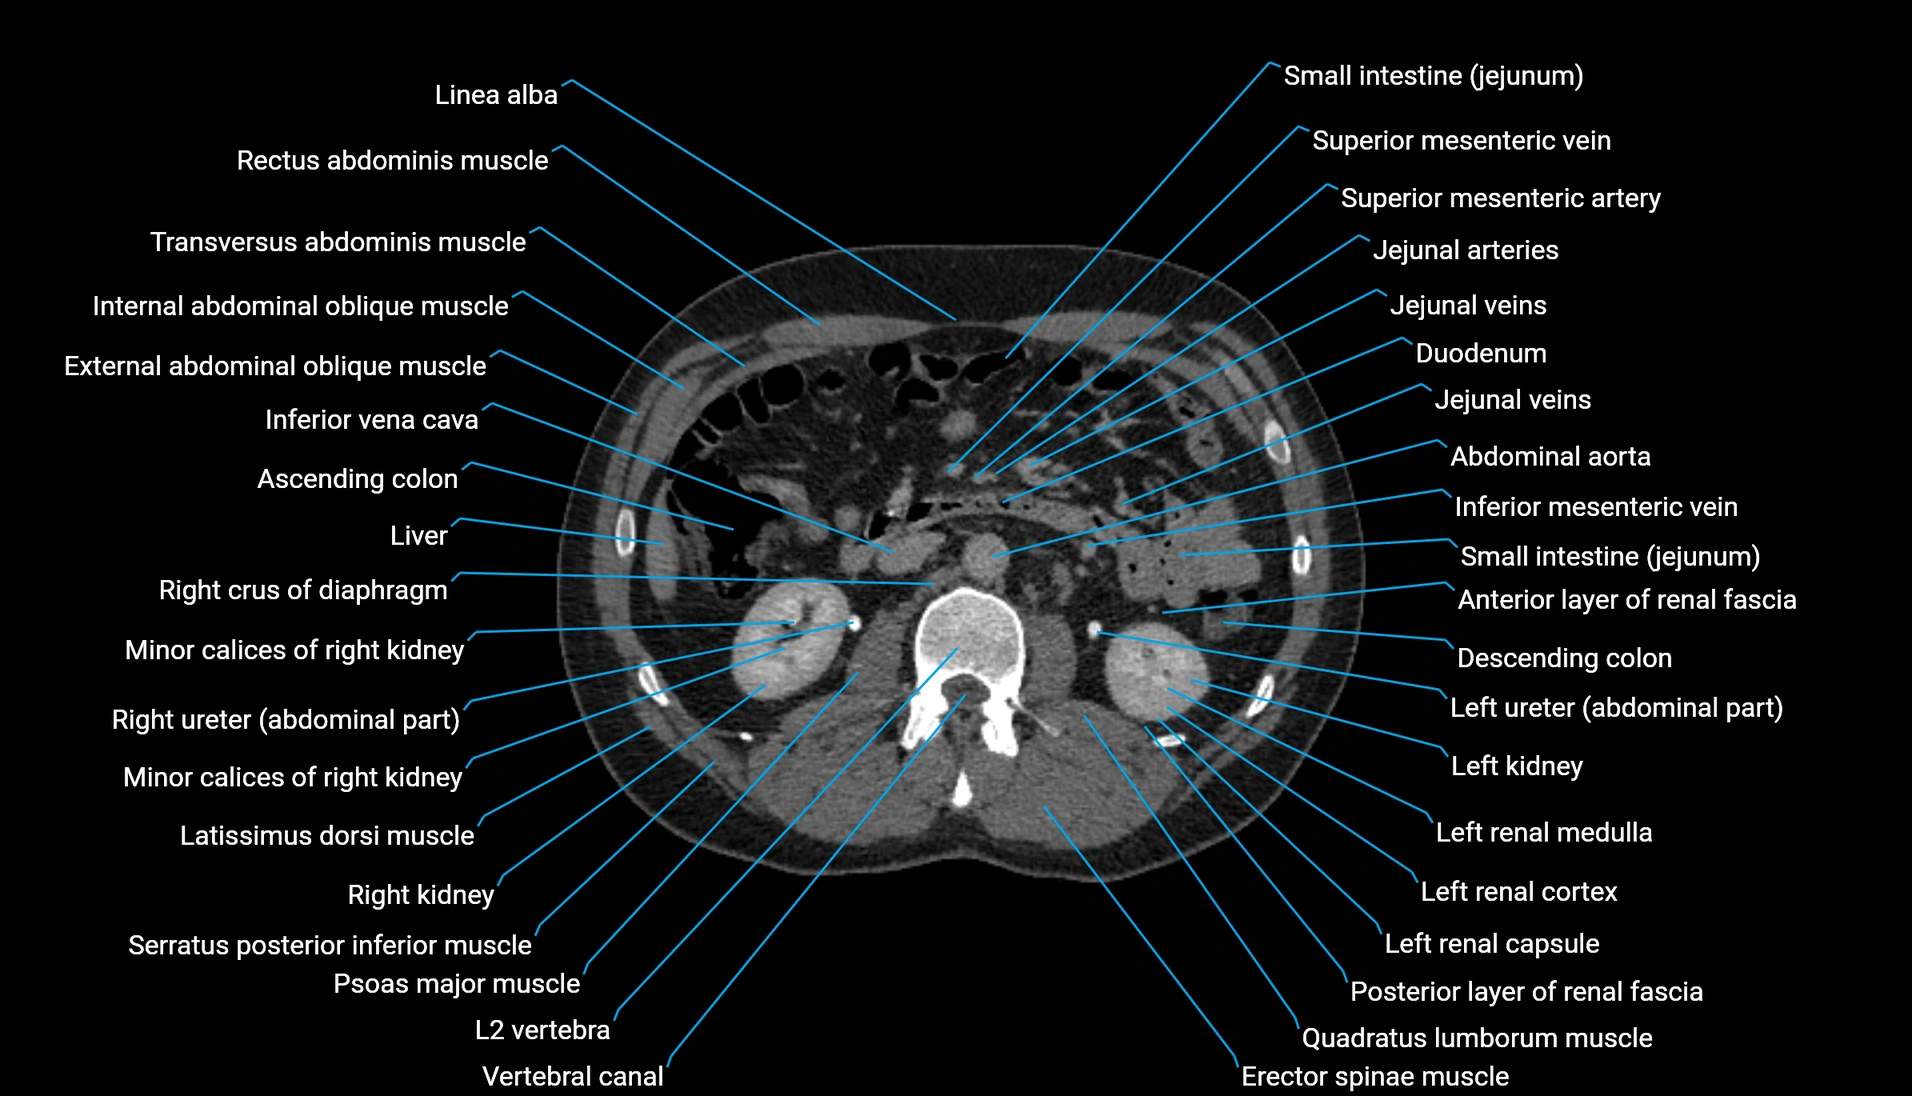

CT Appearance

Non-contrast CT:

-

Demonstrates cortical bone of acetabular rim in excellent detail

Detects fractures, dysplasia, retroversion, or bony overcoverage (pincer impingement)

3D reconstructions used in preoperative hip surgery planning

CT VRT 3D image

CT image